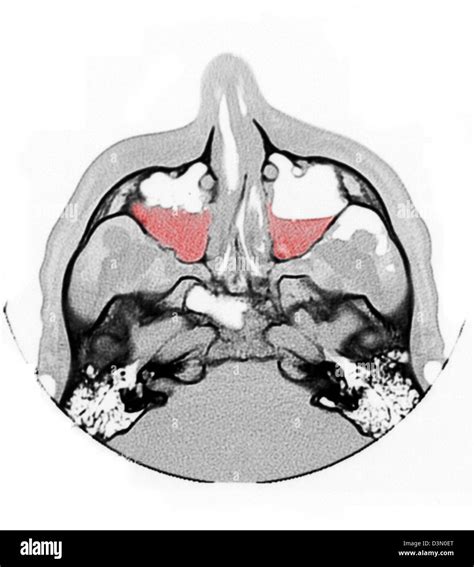

A Mxailliary Sinus CT scan, or Computed Tomography scan, is a non-invasive imaging procedure that uses X-rays to create detailed cross-sectional images of the sinuses. These images help doctors to identify abnormalities, infections, or structural issues within the sinuses. The scan is particularly useful for diagnosing conditions such as sinusitis, nasal polyps, and tumors.

The Mxailliary Sinus CT scan works by taking multiple X-ray images from different angles around the body. These images are then processed by a computer to create cross-sectional views of the sinuses. The resulting images provide a detailed view of the sinus cavities, allowing doctors to identify any abnormalities.

The results of a Mxailliary Sinus CT scan are interpreted by a radiologist, who will look for signs of:

• Inflammation: Swelling or infection in the sinuses.

• Obstruction: Blockages in the sinus passages.

• Abnormal Growths: Polyps, tumors, or other growths.

• Structural Issues: Deviated septum or other structural abnormalities.

Common Findings in a Mxailliary Sinus CT Scan

Some common findings in a Mxailliary Sinus CT scan include:

• Sinusitis: Inflammation of the sinuses, often due to infection.

• Nasal Polyps: Benign growths in the nasal passages.

• Tumors: Abnormal growths that may be benign or malignant.

• Fractures: Bone fractures in the sinus area, often due to trauma.

• Deviated Septum: A misaligned nasal septum that can cause obstruction.